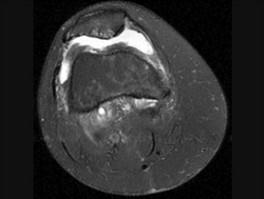

髌骨软骨软化症(如图)的治疗原则哪项是错误的 ( )A、非甾体类抗炎药B、一旦发现尽可能早手术治疗C、物理治疗D、关节内封闭 ...

问题 髌骨软骨软化症(如图)的治疗原则哪项是错误的 ( )

选项 A、非甾体类抗炎药 B、一旦发现尽可能早手术治疗 C、物理治疗 D、关节内封闭 E、股四头肌锻炼

答案 B